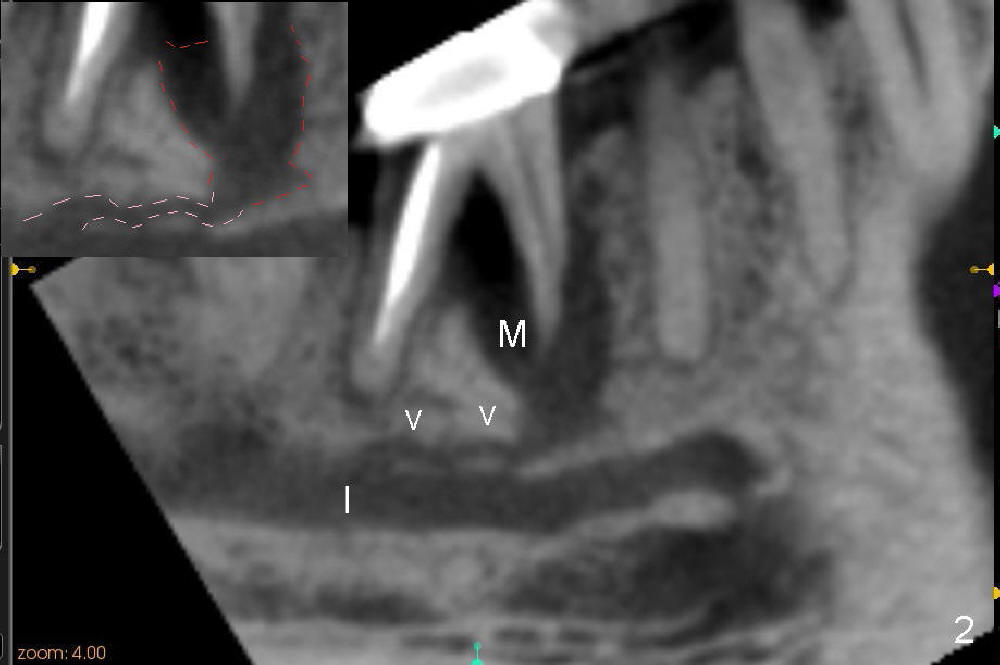

The tooth #30 of a 64-year-old man has endo failure with large radiolucency in the mesial socket (Fig.1 (PA), 2 (CT)).  The tooth is nonsalvageable.  The mesial lesion is closer to the inferior alveolar nerve (I/IAN) than the distal apex.  In addition, there is a connection (Fig.1,2 arrowheads and Fig.2 insert pink dashed line) between the mesial lesion and the nerve.  What is the connection, as related to extraction and immediate implant?

There are three potential spaces for the immediate implant: the mesial and distal sockets and the septum.  First at all, the tooth should be extracted with curettage of granulation tissue from the mesial apical lesion.  The latter turns out to be difficult, since the bottom of the mesial socket has abrupt transition into a narrow neck, which look and feels like the IAN.  To determine the depth of the lesion relative to the IAN, PA is taken (Fig.3) without too much information.  When a radiopaque material in placed in the mesial socket (Fig.4 M), the lesion has apparently not extended to the IAN.  Curettage of the remaining granulation tissue is now an easy task.  Finally bleeding comes from a small hole, as indicated by arrowhead.  Therefore the special structure is a branch of the inferior alveolar vessels.

As to where to place an implant, we try to engage the largest tap (8 mm in diameter) into the mesial socket without binding. The buccal plate of the mesial socket is missing.  It is risky to extend osteotomy in the mesial socket.  Besides, the septum (Fig. 4 S) is not as tall as the distal socket (D).  It appears that the distal socket is the safest place to place an implant.  Furthermore, no drill is used for distal osteotomy.  Instead two osteotomes (3.5x15 and 4x15 mm tapered osteotomes) are used to expand the distal socket with intention to push the septum mesially.  Since the bone density is high, the osteotomes seem not to work as effectively as expected.  Then a 4.5x17 mm tap is placed at the depth ~ 14 mm with stability (Fig.5).  Finally a 5x14 mm tissue-level implant is placed with insertion torque >60 Ncm (Fig.6).  Allograft is placed in the mesial socket and buccal aspect of the distal socket, followed by insertion of collagen plug and membrane (Fig.7).  After insertion of an abutment (Fig.8 (taken 6 days postop) *), perio dressing (P) is applied to cover the wound.  There is no postop paresthesia.